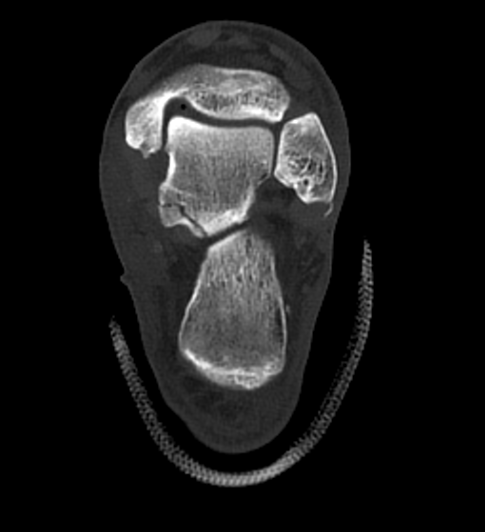

2025年国庆中秋双节期间,58岁的患者赵大哥(化名)紧急被送往北大人民青岛医院成人急诊科。约2小时前,他不慎被重物砸伤左足踝部,当即出现剧烈肿痛。经CT检查,赵大哥左侧距下关节脱位,同时伴有左距骨、腓骨、跟骨多处骨折,以及距腓前韧带断裂、距骨软骨损伤。

△左上、左下、右侧图片分别为术前三维侧面、后面、前面